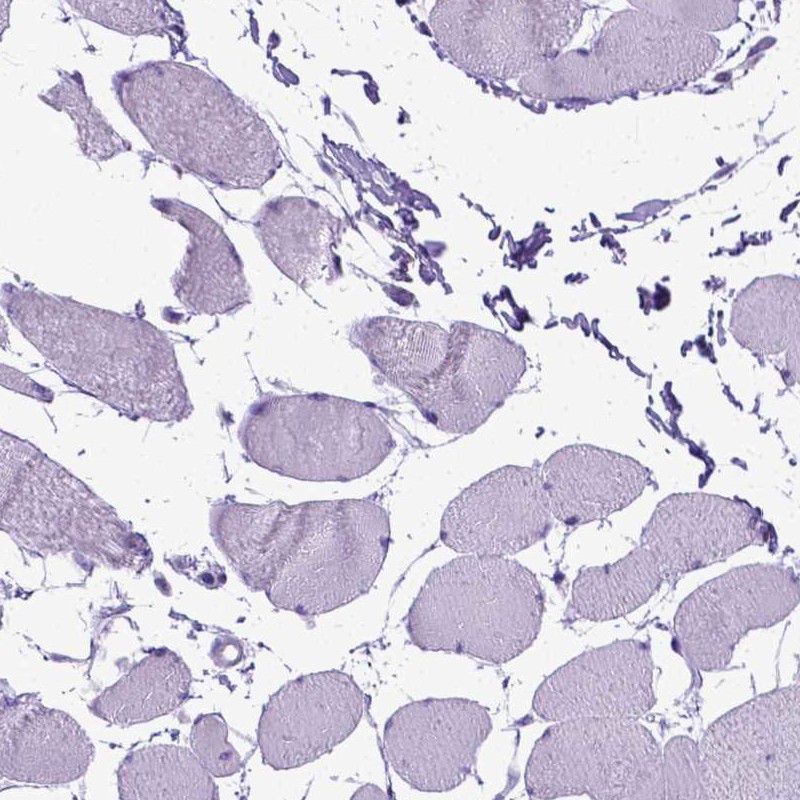

Immunohistochemistry analysis in human esophagus and skeletal muscle tissues using Anti-PPL antibody. Corresponding PPL RNA-seq data are presented for the same tissues.